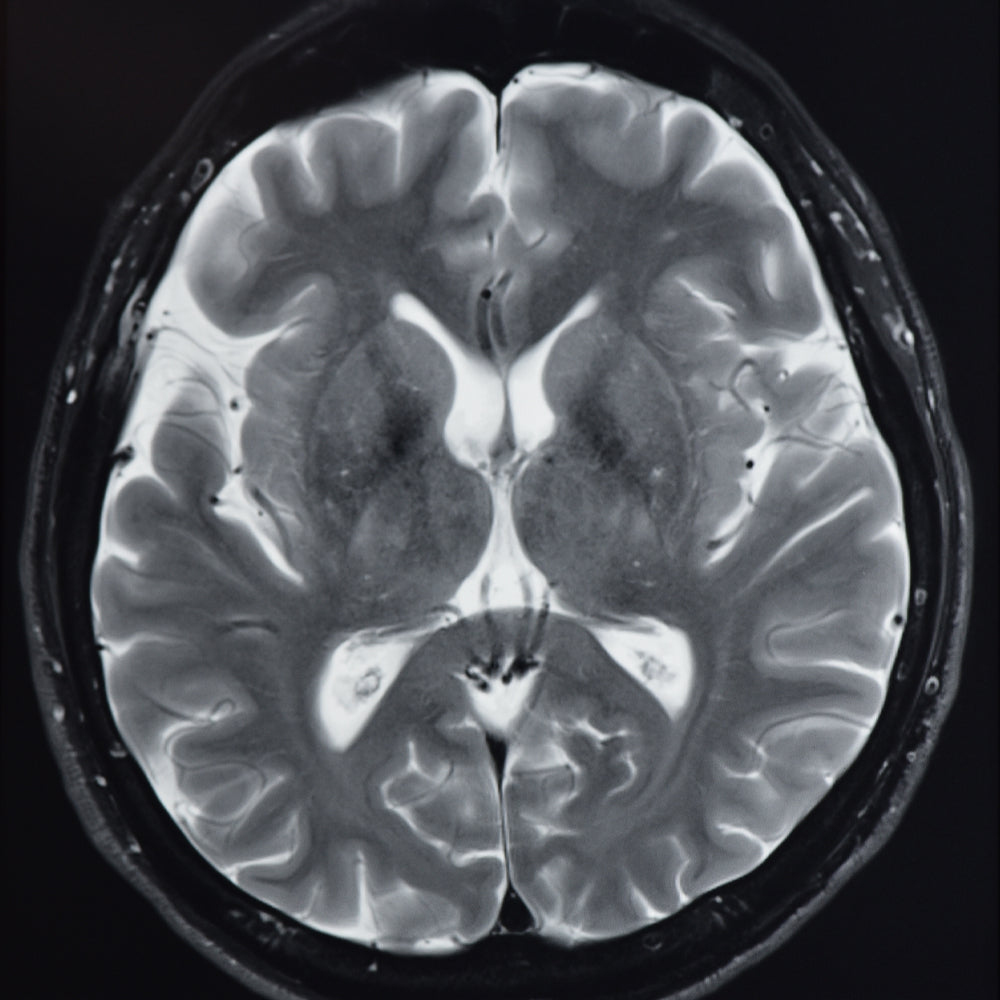

If you're looking to maximise your sleep, energy and focus, Muse is a great tool to help you get there. I use the Muse S Athena, a revolutionary cognitive tracker that combines EEG and fNIRS technologies to deliver real-time feedback on focus and endurance. It does this through brainwave and blood flow tracking, giving me insight into my nervous system and allowing me to focus on areas that need improvement. Overnight, it tracks light, REM and deep sleep stages, and uses responsive bedtime stories that gently cue the brain for deeper, restorative sleep. It's comfortable to wear and part of my wellness toolkit I couldn't live without.